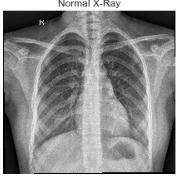

Fig-1:NormalCXRImages Fig-2:PneumoniaAffectedCXRImages